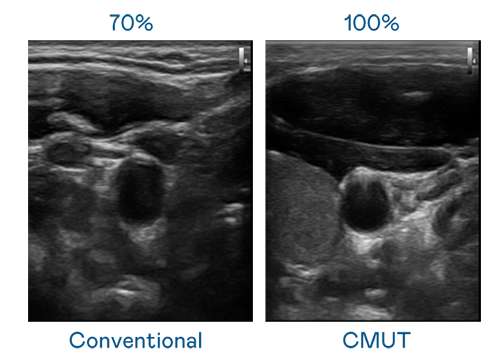

CMUT 技術是一種用電容式微機電元件來產生超音波訊號的技術。與傳統 PZT 壓電式技術相比,CMUT 頻寬增加 30%,更寬頻的超音波訊號讓影像解析度大幅提升,是實現高影像品質醫療超音波掃描、促進精準醫療發展的關鍵技術。

超音波影像的解析度高低,首先取決於探頭能發出的訊號頻寬。威尼斯人 CMUT 可提供高清晰的超音波訊號,提供高頻寬、高靈敏度、影像紋理細節更高的超音波影像,協助醫護人員縮短影像判讀時間及利用精準的醫療影像進行診斷。